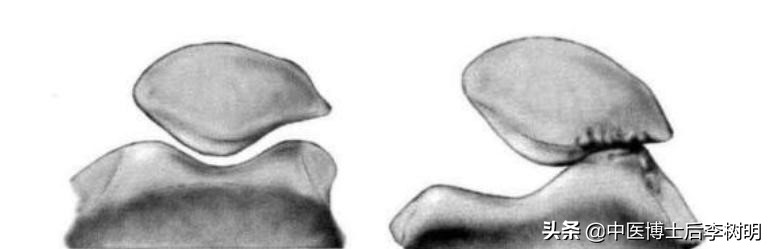

髌骨周围肌力不均衡,引起髌骨过度外倾,导致髌骨运动轨迹外移。 造成髌骨及股骨滑车软骨受力不均匀,引起软骨损伤从而导致严重的髌股关节运动障碍。

铍针治疗的原理是,精确松解紧张的髌骨外侧支持带和髂胫束,明显降低外侧髌股关节面的压力,帮助髌骨恢复正常力线,从而避免软骨的快速磨损。

一句话,铍针治疗,帮助髌骨回归“正轨”,纠正了关节力线,避免了软骨的破坏。从根源上解决疼痛。